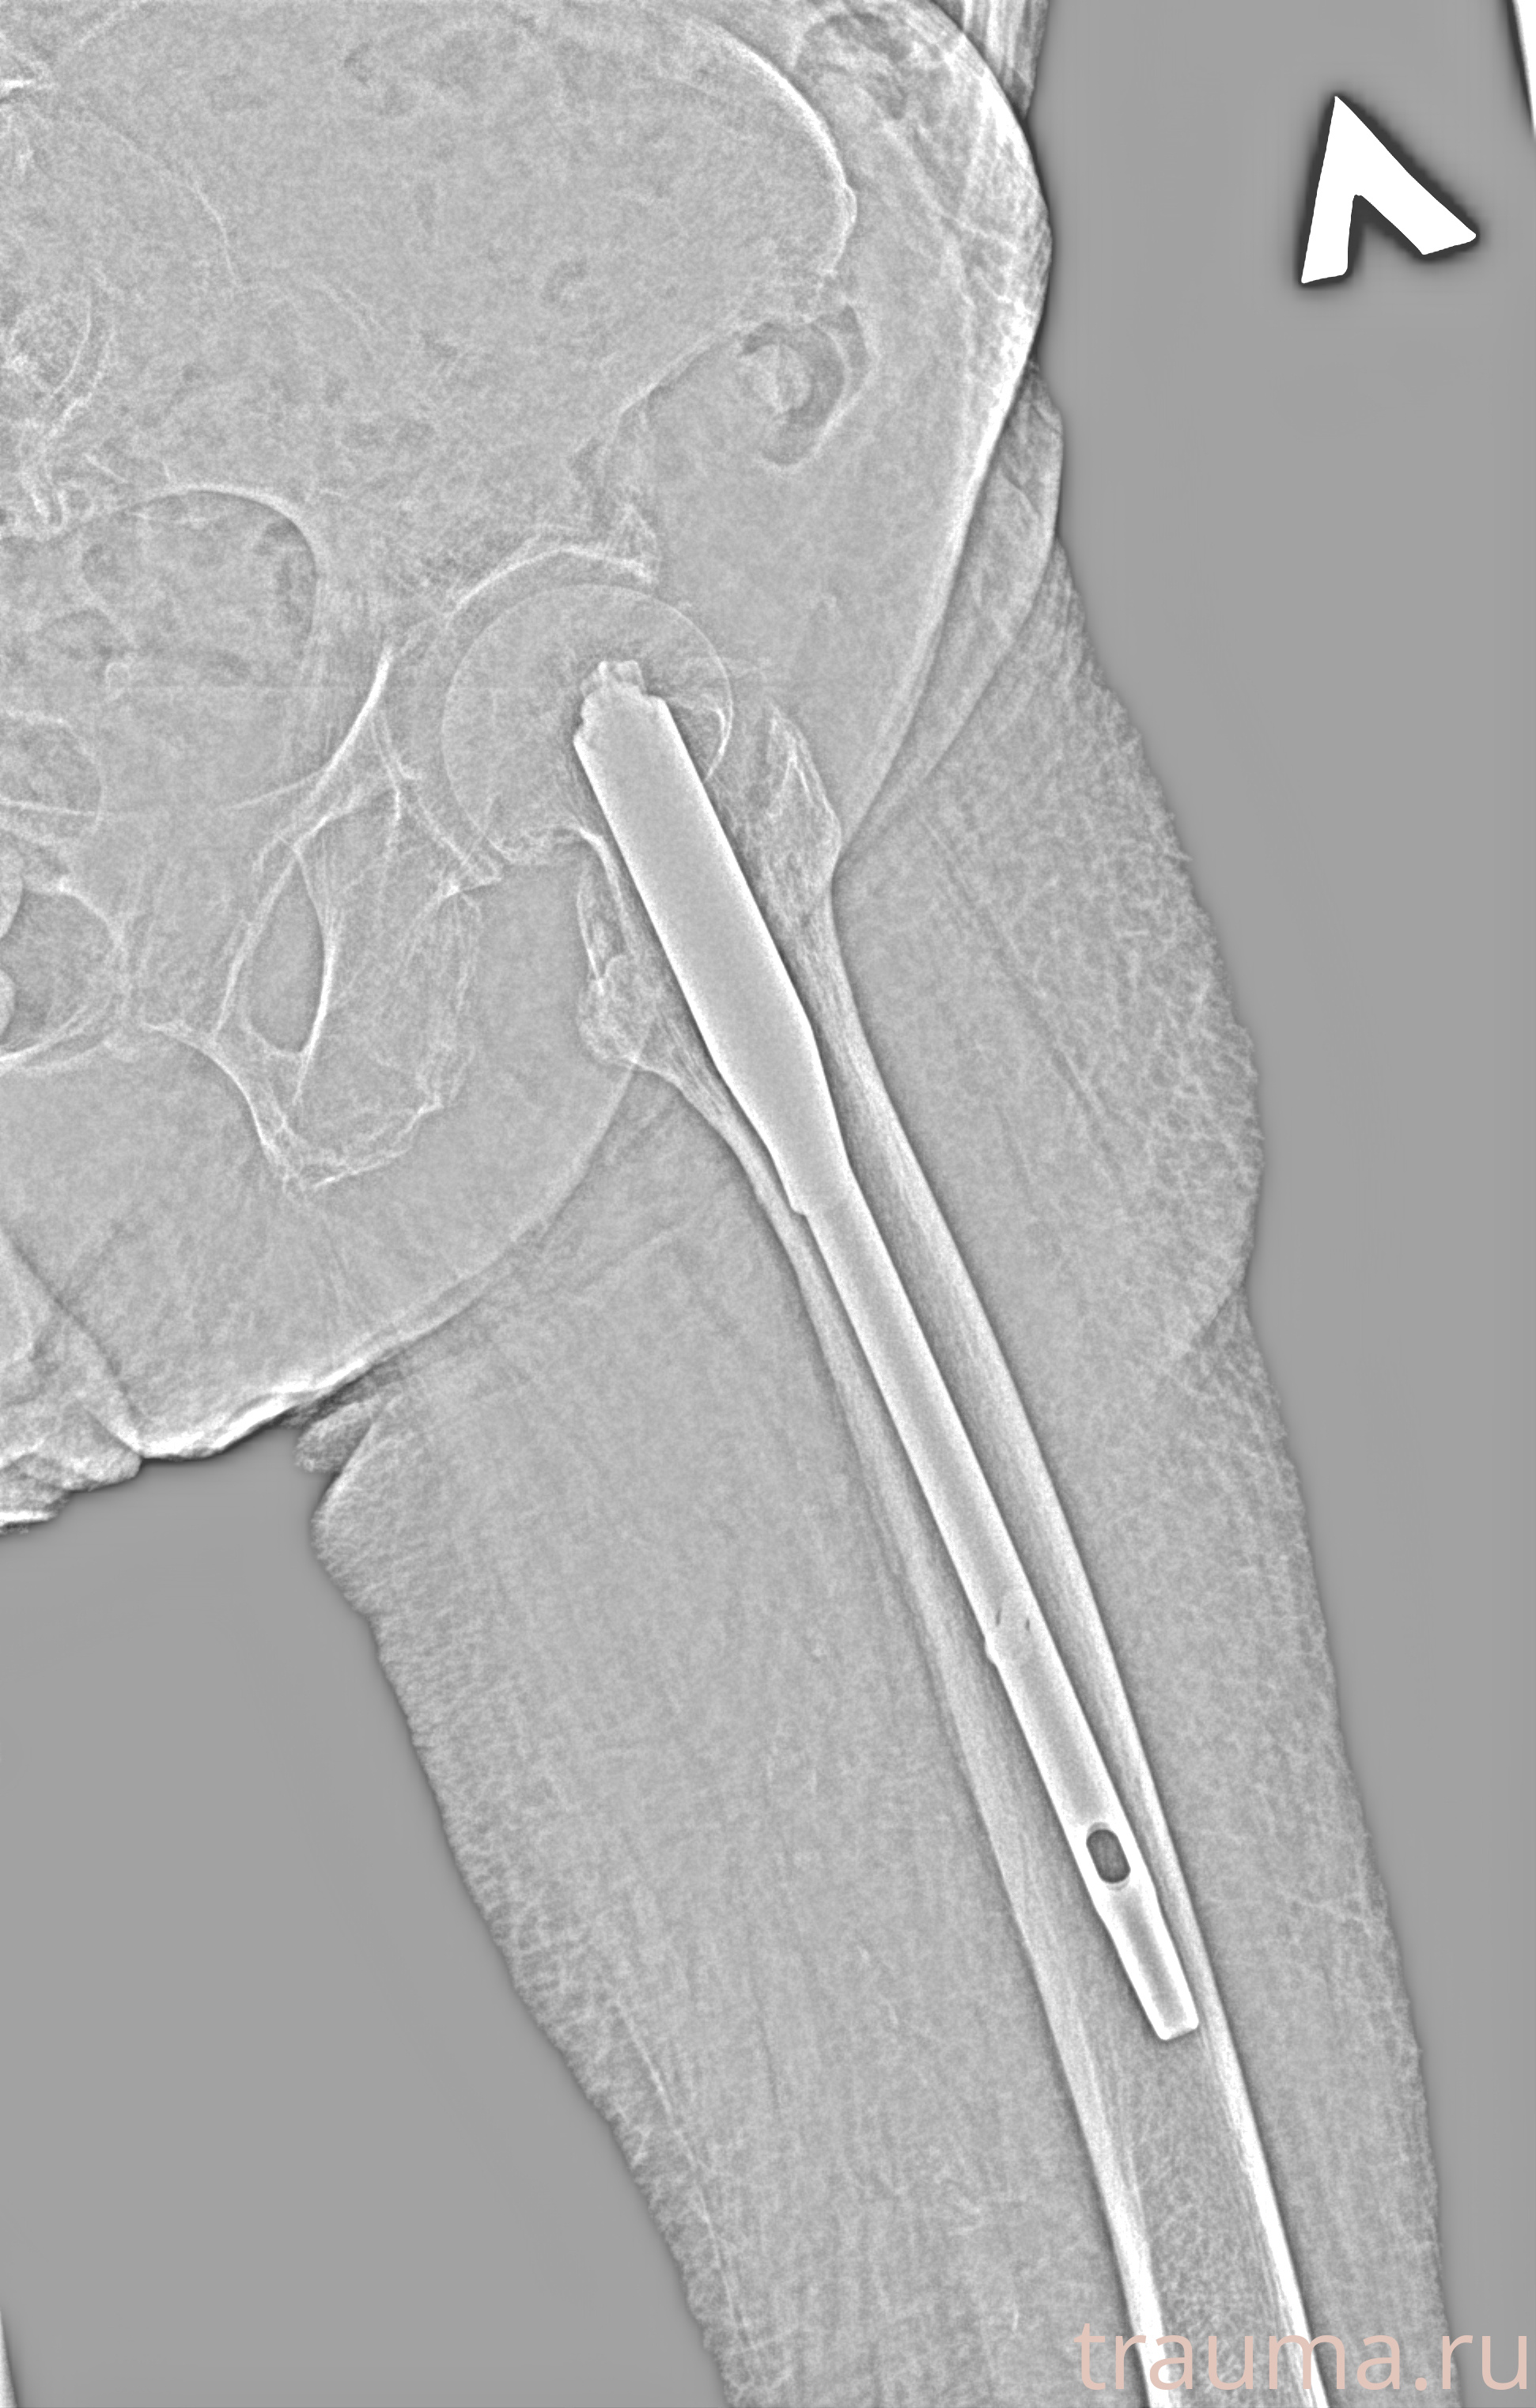

Рентген на дому: по вашему адресу приезжает врач-рентгенолог, травматолог-ортопед с мобильным рентгеновским аппаратом, проводит диагностику травмы или заболевания, делает необходимые рентгенограммы, дает рекомендации по дальнейшему лечению. Получить качественные снимки в домашних условиях возможно благодаря уникальной методике, разработанной МосРентген Центром для института  Склифосовского